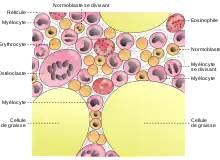

Les cellules souches hématopoïétiques produisent tous les types de cellules sanguines. Ces cellules sont peu nombreuses, ne représentant qu'une cellule sur 10 000 à 15 000 cellules de la moelle osseuse. Elles peuvent aussi s’échapper dans le sang, mais ne représentent dans ce cas qu'une cellule sur 100 000 cellules sanguines[14]. Des protéines spécifiques, dépendantes des besoins, vont inciter ces cellules à se diviser et à produire les différentes cellules sanguines. De plus, elle se divisent aussi afin de se reproduire et ainsi garantir la production continue de cellules sanguines[15].

Les cellules souches hématopoïétiques se divisent dans un premier temps en deux types de cellules différentes, les cellules myéloïdes progénitrices qui vont donner les cellules rouges, les cellules blanches et les plaquettes, et les cellules lymphoïdes progénitrices qui vont donner les lymphocytes. Quand les cellules sanguines arrivent à maturation, elles sont libérées dans le sang[15]. Ces progéniteurs peuvent produire beaucoup de cellules, mais seulement pendant un temps limité après leur création[14]. On estime qu'il faut entre 15 et 20 jours pour que les cellules sanguines viennent à maturation, mais cette durée peut varier selon les besoins[2].

Dépendant de leurs localisations, les cellules souches hématopoïétiques ou les cellules progénitrices vont se spécialiser différemment. Ces localisations, les niches de cellules souches (en), sont définies par les cellules environnantes comme les adipocytes, les ostéoblastes, les vaisseaux sanguins, les cellules stromales[16].

Les globules rouges en formation s'agglutinent autour d'un macrophage et forment ainsi des îlots d'érythroblastes. Ces îlots sont proches des capillaires. Les cellules les plus proches du macrophage sont les moins matures. Le macrophage absorbe les cellules défectueuses et enlève aussi les noyaux des globules rouges avant qu'elles ne gagnent les vaisseaux sanguins[13].

- les neutrophiles : Ce sont les globules blancs les plus abondants, constituant presque la moitié[13] de tous les leucocytes dans la moelle osseuse, et mesurant de 0,010 à 0,012 mm. Ils s’attaquent principalement aux bactéries et aux champignons en utilisant des enzymes comme la lysozyme et la défensine, et ingèrent les débris inutiles[20],

- les éosinophiles : Elles représentent environ 6 %[13] des globules blancs et mesurant de 0,010 à 0,012 mm[20]. Elles combattent les parasites comme les vers et sont aussi antihistaminique, c'est-à-dire qu'elles aident à réduire les allergies[19],

- les basophiles : Ce sont les globules blancs les moins abondants, représentant moins de 1 %[13] du total. Ils mesurent de 0,008 à 0,010 mm[20] et jouent un rôle dans l'intensification des inflammations et dans la prévention de la coagulation ;

- les monocytes : Ces larges cellules de 0,12 à 0,020 mm représentent 5 %[13] des globules blancs de la moelle osseuse. Quand ils sont libérés dans le sang, ils sont encore immatures et y restent deux jours avant de se fixer dans un tissu (y compris la moelle osseuse) où ils grandissent pour devenir des macrophages et ingurgiter tous les débris non-désirés. Lorsqu'ils ont accompli cette tâche, qui peut durer des années, ils meurent ;

- les lymphocytes : Ces cellules, à tous les stades de la maturation, représentent presque 40 %[13] des globules blancs et varient en dimensions de 0,006 à 0,017 mm[20]. Il a 3 types de lymphocytes, les lymphocytes NK, B et T. Les lymphocytes NK peuvent reconnaitre des cellules qui sont étrangères ou qui ont des signes d'anormalité comme les cellules cancéreuses[20]. Les lymphocytes B produisent des marqueurs qui s’accrochent à des cellules étrangères, les désignant ainsi comme cellules à éliminer. Les lymphocytes T s'attaquent à des cellules étrangères spécifiques et les détruisent[19]. Les lymphocytes B sont créés dans la moelle osseuse mais migrent vers les tissus lymphoïdes pour achever leur maturation et leur différenciation. Les lymphocytes T ne sont produits dans la moelle osseuse que pendant le stade fœtal et la petite enfance, puis le thymus prend la relève[21].

Tous les globules blancs granuleux et les monocytes sont uniquement produits dans la moelle osseuse où ils maturent en passant par plusieurs phases ; leurs productions sont stimulées par des protéines appropriées[19].